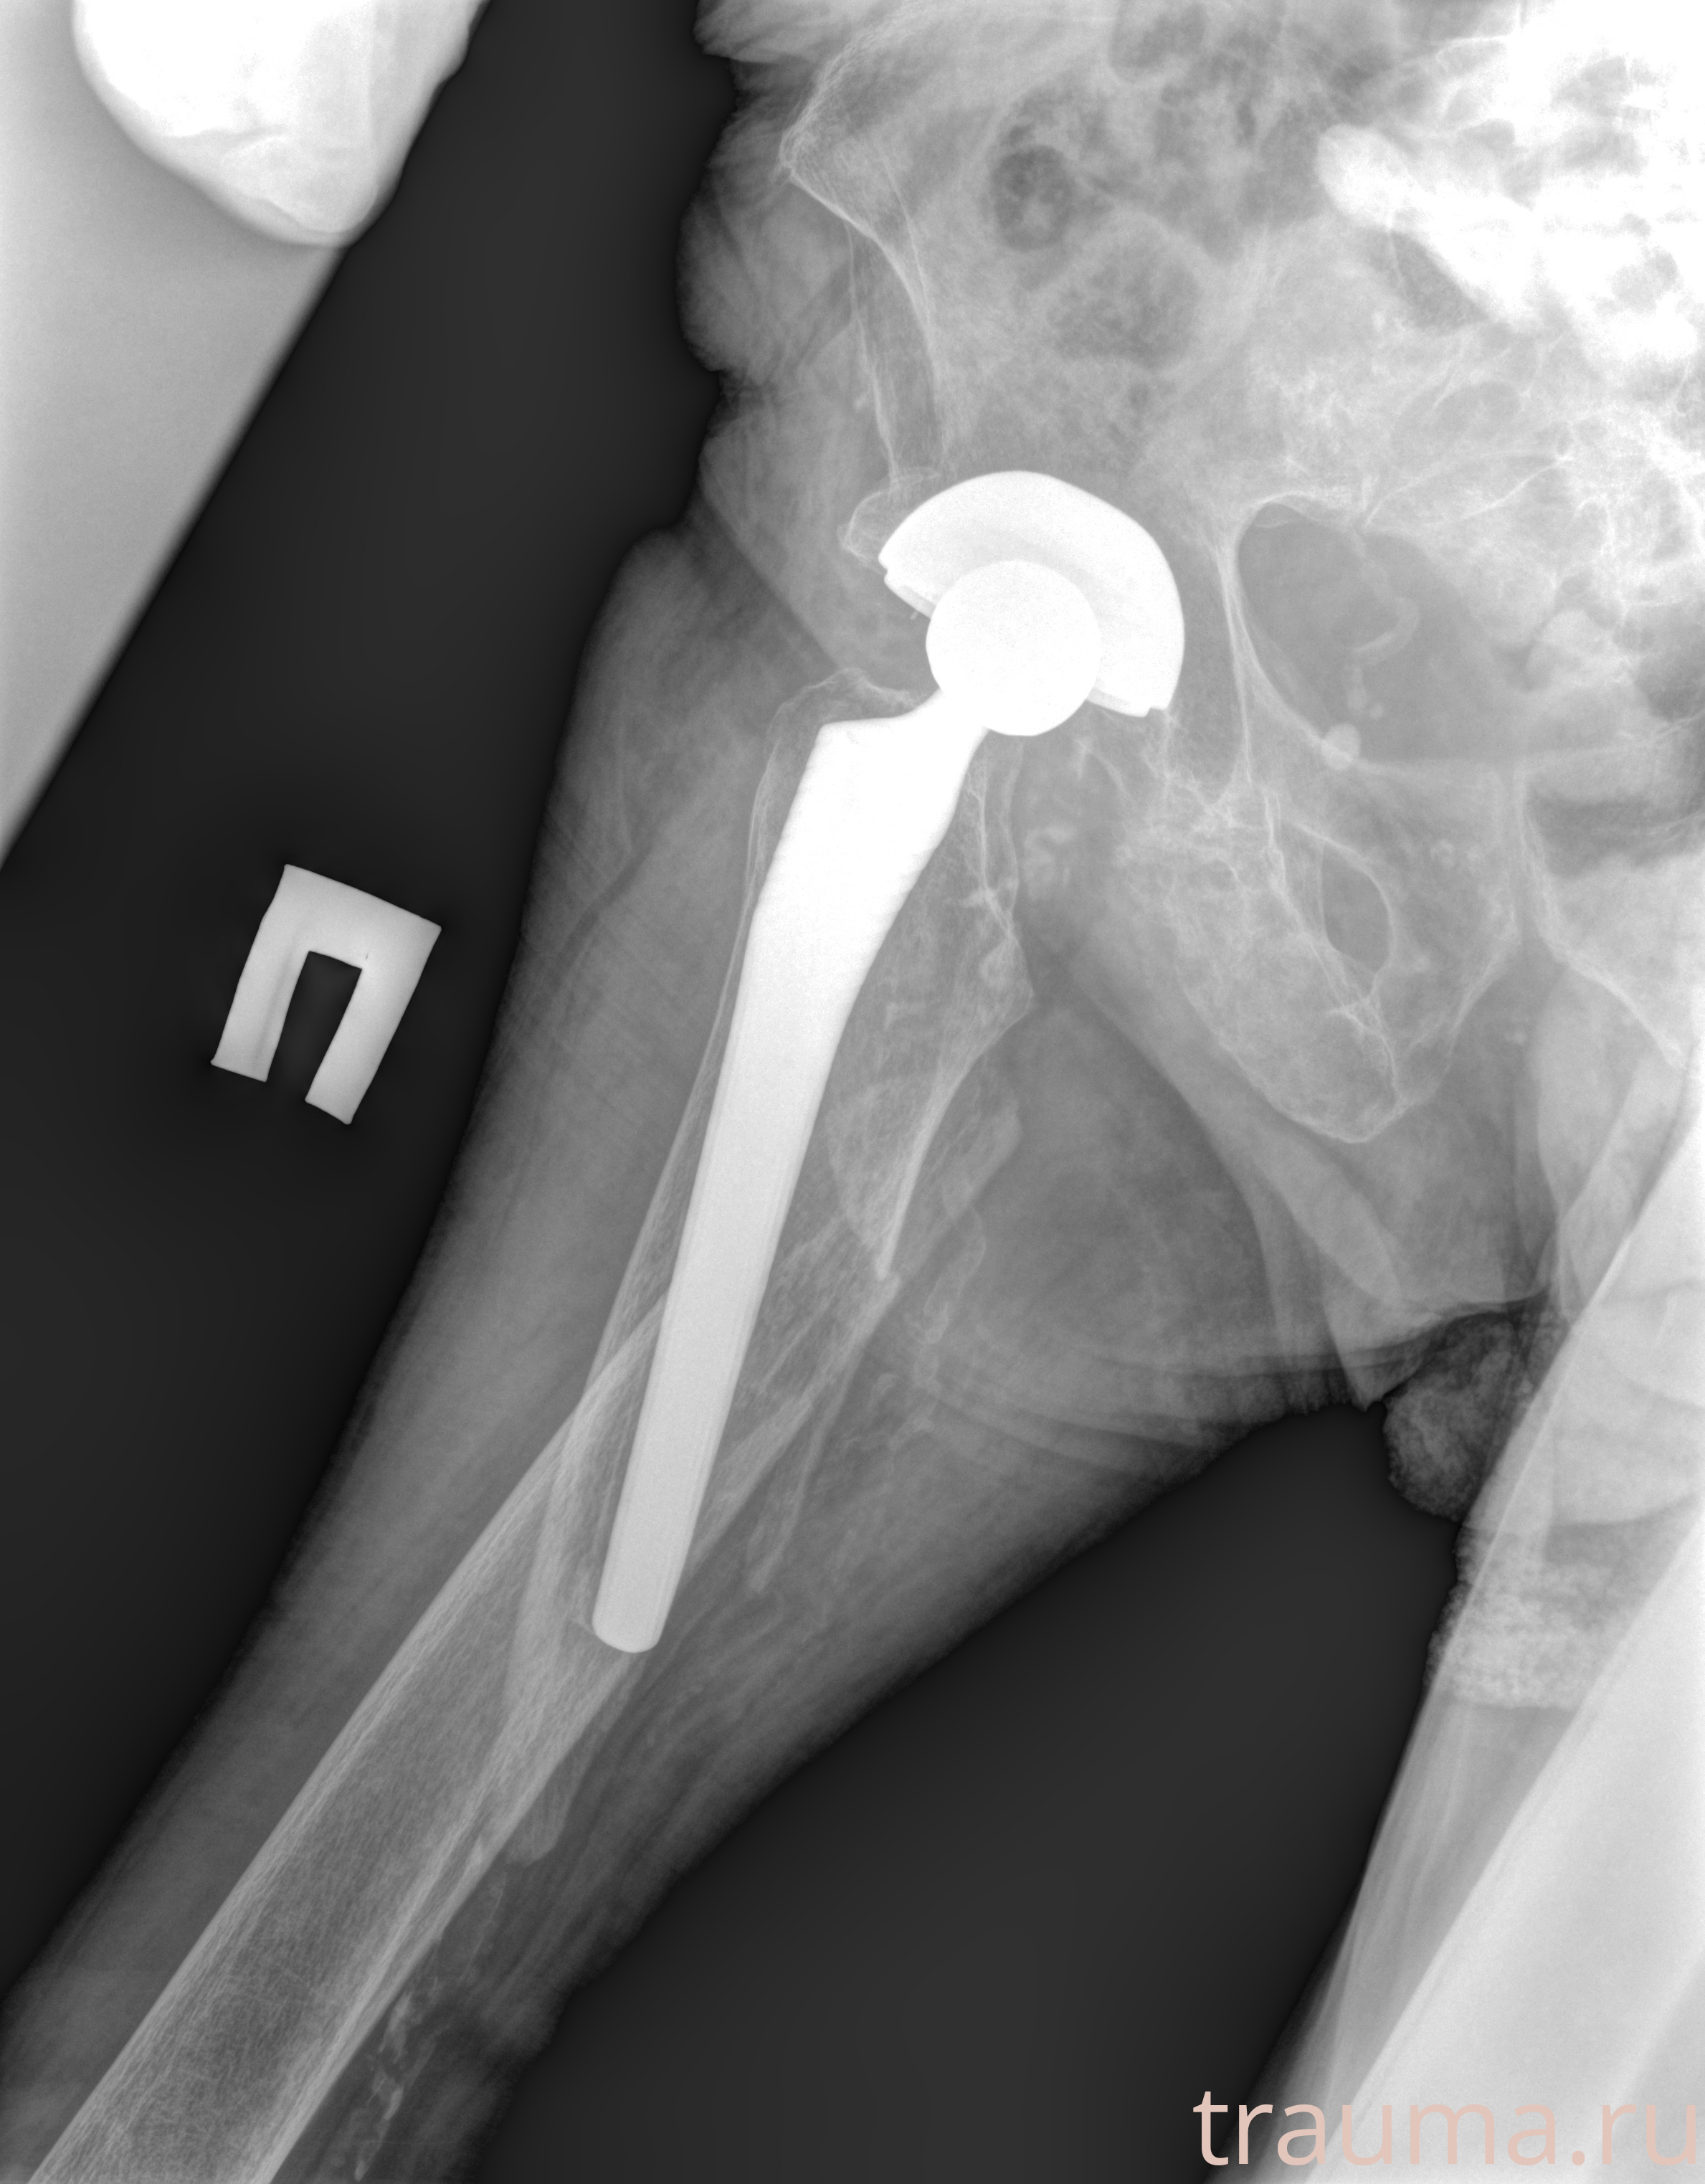

Рентгенограммы

Рентген на дому: по вашему адресу приезжает врач-рентгенолог, травматолог-ортопед с мобильным рентгеновским аппаратом, проводит диагностику травмы или заболевания, делает необходимые рентгенограммы, дает рекомендации по дальнейшему лечению. Получить качественные снимки в домашних условиях возможно благодаря уникальной методике, разработанной МосРентген Центром для института  Склифосовского